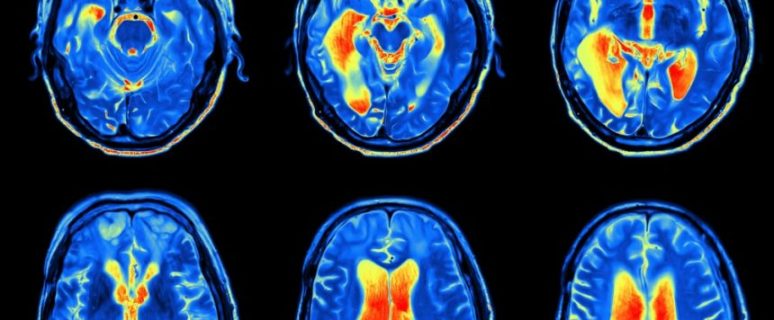

מאת: עופר בן חורין. סריקת ה-fMRI, אשר הוצגה לראשונה בשנת 1990, נועדה על מנת לאתר איזורים אשר מופעלים במוח כתוצאה מביצוע משימות או כתוצאה מגירוי חושי- למשל נגיעה באף או כיווץ של שריר מבטאים את עצמם במוח, וה-fMRI נועד לזהות את האיזור המופעל במוח בתגובה לכך. הפוסט נועד להזביר מה באמת קורה בתחום סריקת ה-fMRI.